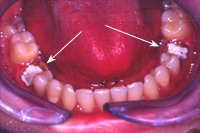

Der allgemeine zahnärztliche Check-up ergab nebst vielen anderen kariösen Zähnen zwei bis auf das Zahnfleisch abgefaulte Unterkiefermolaren (Abb. 1). Da die beiden Zähne wegen alten, insuffizienten Wurzelbehandlugen beherdet waren, hat meine Tochter Vanessa zuerst korrekte Wurzelbehandlungen durchgeführt (für die Bilder dazu s. Kapitel Endodontie, Fall 2). Danach folgte die Instruktion in Mundhygiene und Prophylaxe, da eine Wiederherstellung der Zähne grundsätzlich nur auf gesundem Fundament (s. Prophylaxe) und mit guter Mundhygiene langfristig Sinn macht.